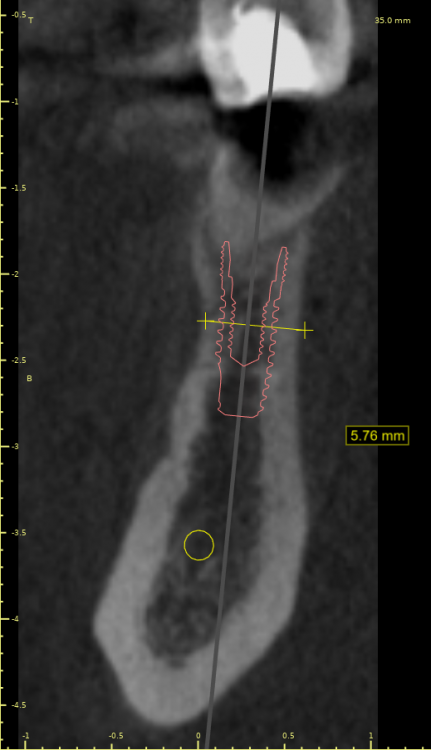

Женька Опубликовано 19 июля, 2021 Автор Поделиться Опубликовано 19 июля, 2021 @Евгений Ходыкин Глубже этого "перешейка" тонкого? планирую вот так Ссылка на комментарий

Женька Опубликовано 20 июля, 2021 Автор Поделиться Опубликовано 20 июля, 2021 @Irouil а что по утоплению? ставить ещё глубже, или по планируемому срезу достаточно? Ссылка на комментарий

Irouil Опубликовано 20 июля, 2021 Поделиться Опубликовано 20 июля, 2021 Ставить по ортопедии Ссылка на комментарий

Евгений Ходыкин Опубликовано 22 июля, 2021 Поделиться Опубликовано 22 июля, 2021 20.07.2021 в 18:31, Женька сказал: @Irouil а что по утоплению? ставить ещё глубже, или по планируемому срезу достаточно? Ещё глубже Ссылка на комментарий

Евгений Ходыкин Опубликовано 23 июля, 2021 Поделиться Опубликовано 23 июля, 2021 @Женька шейка ниже жёлтой линии, которую нарисовали. 1 Ссылка на комментарий

Женька Опубликовано 23 июля, 2021 Автор Поделиться Опубликовано 23 июля, 2021 @Евгений Ходыкин Ого как глубоко… а как потом это проснять, и кость формиком не раздавить? Ссылка на комментарий

Евгений Ходыкин Опубликовано 24 июля, 2021 Поделиться Опубликовано 24 июля, 2021 10 часов назад, Женька сказал: @Евгений Ходыкин Ого как глубоко… а как потом это проснять, и кость формиком не раздавить? Профилируете кость, разумеется Ссылка на комментарий

Irouil Опубликовано 26 июля, 2021 Поделиться Опубликовано 26 июля, 2021 Я бы придал имплантам немного ангуляции Ссылка на комментарий

Евгений Ходыкин Опубликовано 27 июля, 2021 Поделиться Опубликовано 27 июля, 2021 (изменено) 20.07.2021 в 00:03, Женька сказал: планирую вот так У Вас 3 варианта: 1. Как спланировано на скрине Вашем + можно конденсорами поработать. 2. Топить глубже. 3. НКР 4. Решать, конечно же, Вам)) Изменено 27 июля, 2021 пользователем Евгений Ходыкин 1 Ссылка на комментарий